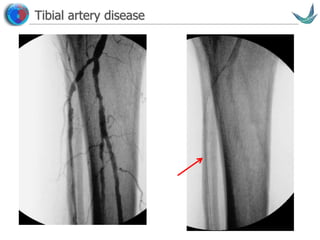

Tibial artery disease